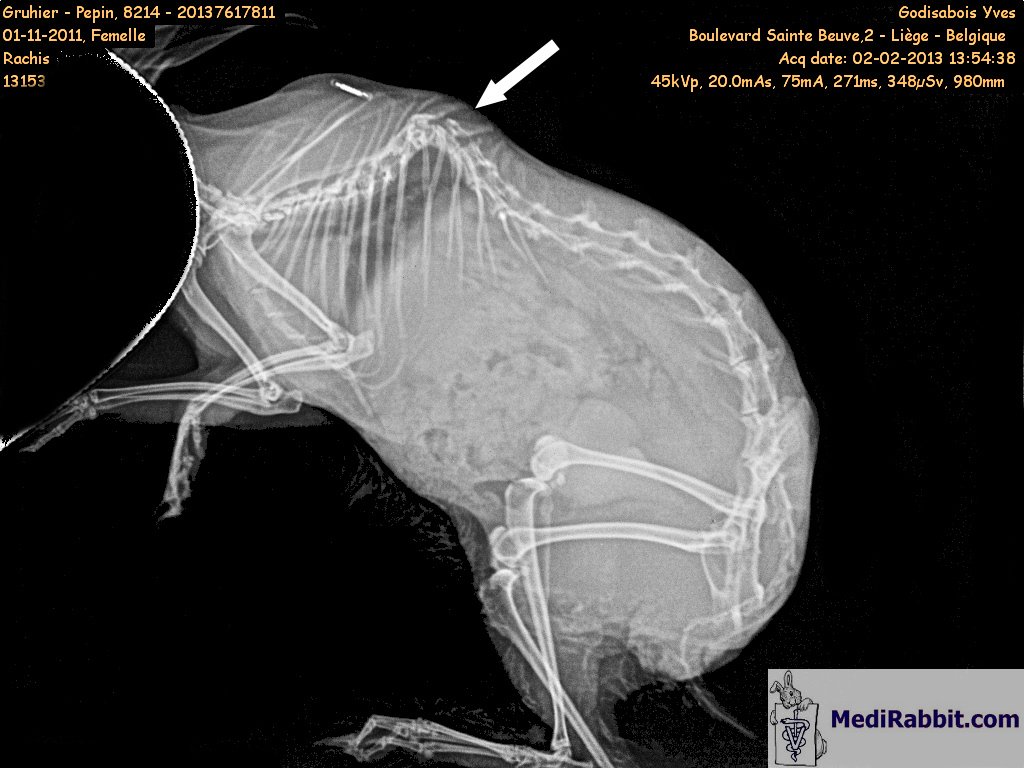

The lateral

and dorso-ventral radiographic views of Pepin

reveal a severe deformity of the spine. A rabbit with such an abnormality

often develops paresis of the lower limbs, a condition that worsens over

time. The degeneration of vertebral discs (spondyloarthropathy) contributes

to the challenging process. The rabbit will experience difficulties grooming

its fur and collecting its caecotropes.

Dr Maassen, cabinet Grodisiabois,

Liège (Belgique) Rabbit

suffering from thoracic lordosis, a deformation of the spine towards the

inside of the body, accompanied by paresis of the posterior limbs. In September, calcium crystals appeared in the urine. Despite treatment, a change in diet, and daily washes, her condition